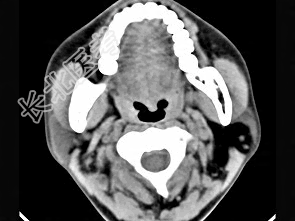

- 单项选择题女性50岁,左侧面部肿胀, CT检查如图,应考虑为 ( )

A、左侧腮腺囊腺瘤

B、左侧腮腺囊肿

C、左侧腮腺脂肪瘤

D、左侧腮腺错构瘤

E、左侧腮腺炎